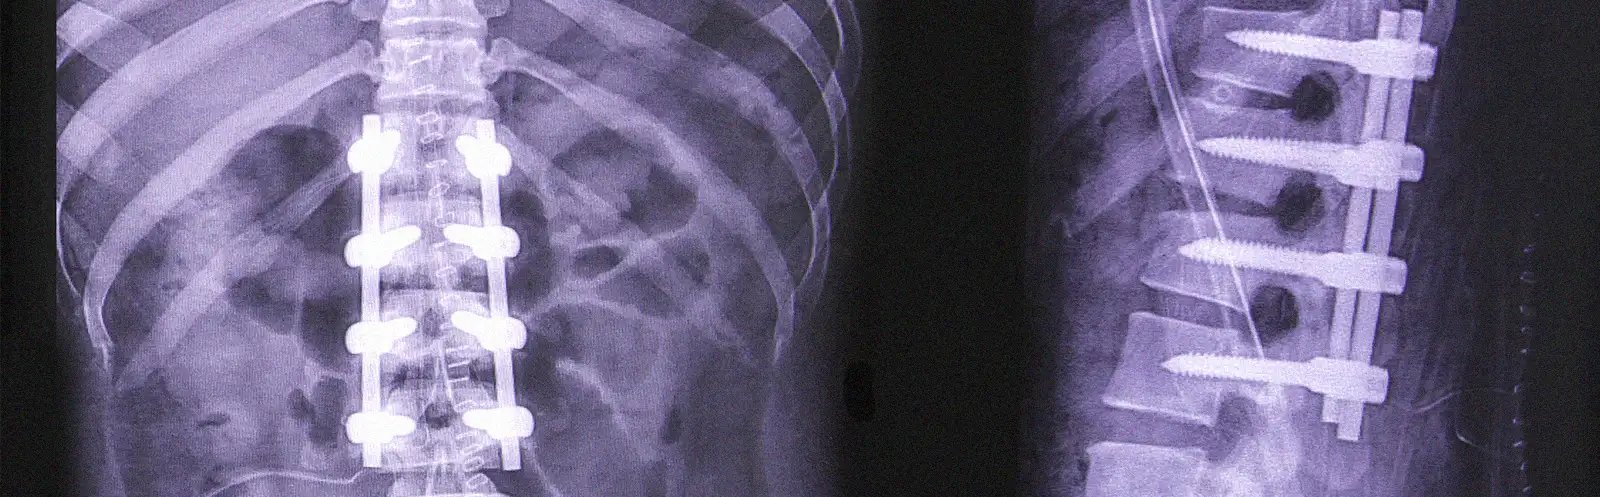

Основной принцип хирургического вмешательства при дегенеративном стенозе поясничного отдела позвоночника — это декомпрессия всех нервных структур, связанных с развитием неврологической симптоматики.

Наиболее часто встречающимися вариантами хирургического лечения являются декомпрессия и/или, в зависимости от особенностей заболевания, ее сочетание со стабилизацией позвоночных сегментов с применением различных имплантатов:

Операция при необходимости может дополняться межтеловой и транспедикулярной стабилизацией поражённого сегмента.